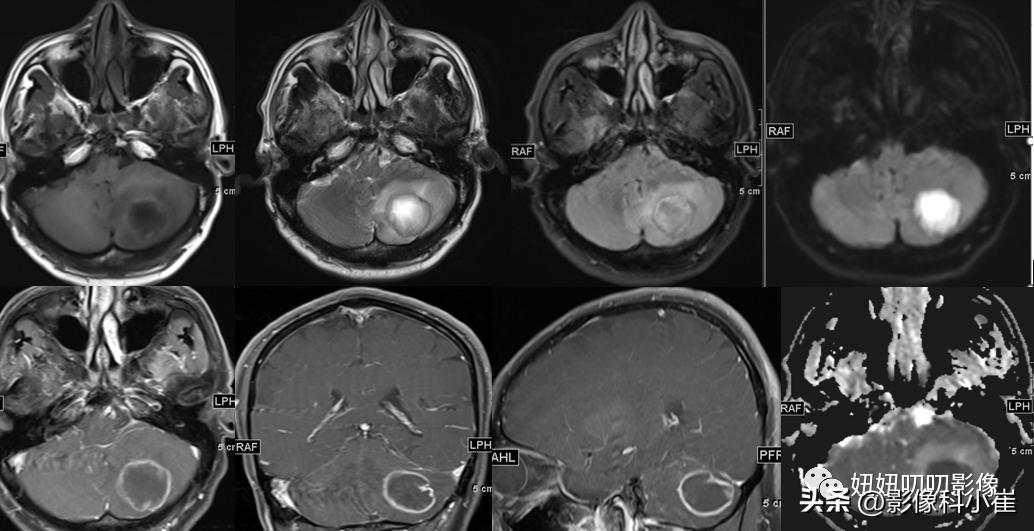

左侧小脑半球片状长短T1等长T2 异常信号,边界不清,大小约3.2X2.9X2.4cm,T2-Flair呈等高信号,周围见斑片状水肿带,DWI 示病变明显弥散受限,增强扫描可见不均匀环状强化。双侧放射冠、皮层下另见少许斑点状等长 T1、长T2 异常信号灶,T2 Flair 呈高信号,DWI未见明显弥散受限,增强扫描未见明显异常强化。第四脑室受压变窄,幕上脑室系统未见明显扩张。脑沟、脑裂略增宽。中线结构无移位。双侧筛窦、上领窦粘膜增厚。

这个病有意思,周边T2黑黑的,弥散受限这么明显,强化还是环形强化,从环形强化入手?转移,胶质母,脓肿。从弥散收入,淋巴瘤,脓肿,胶质母,T1还有出血,信号不均匀,边界清楚。其实看到出血觉得是胶质母,其实看看弥散的均匀度,和环状强化的边,并不是那么花环样子,加上白细胞高,可能还是脓肿。

病理是脓肿;

慢慢对比,看下边界,看下DWI的样子,自己慢慢品!!!